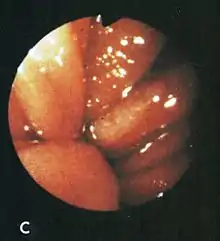

Based on their surgical observations, Windsor and Collis in 1967[4] proposed that blood loss was due to local trauma to the stomach where it rides to and fro in the hiatus on respiration. Boutelier et al.[8] noted on gastroscopy ulcers and erosions at the level of the neck of the hernia in individuals with acute and chronic bleeding, but no detailed description was given. Cameron and Higgins in 1986[1] described linear gastric erosions, later called "Cameron lesions", in people with x-rays showing one-third or more of the stomach above the diaphragm.[9][10][11][12][13][14][15] (figure 1). Over 6 years, Cameron and Higgins studied 109 persons with large hiatal hernias, 55 with anemia and 54 without anemia, at esophagogastroduodenoscopy. Cameron lesions, often multiple, were found at or near the level where the herniated stomach was constricted by the diaphragm. The lesions were typically white, superficial, linear, and oriented along the crests of inflamed appearing mucosal folds (figure 2). Small amounts of blood were often seen on the lesions (Fig 3). Mucosal folds at the diaphragm level were often seen rubbing against each other on respiration (Fig 4). It was proposed that the lesions were caused by mechanical trauma at the level of constriction by the diaphragm [1] Cameron lesions were found in 42% of persons with anemia compared to 24% in those without anemia, a statistically significant difference, p<0.05. Spots of fresh or clotted blood were seen on the lesions in 25% of persons with anemia compared to 7% without anemia, also a significant difference, p<0.05. In the 109 persons in this study, 15 had reflux esophagitis, 11 had peptic ulcers, and 7 had Barrett's esophagus, but none of these findings correlated with anemia. Thus, in people with large hernias, Cameron lesions with evidence of slow bleeding were associated with iron deficiency anemia.